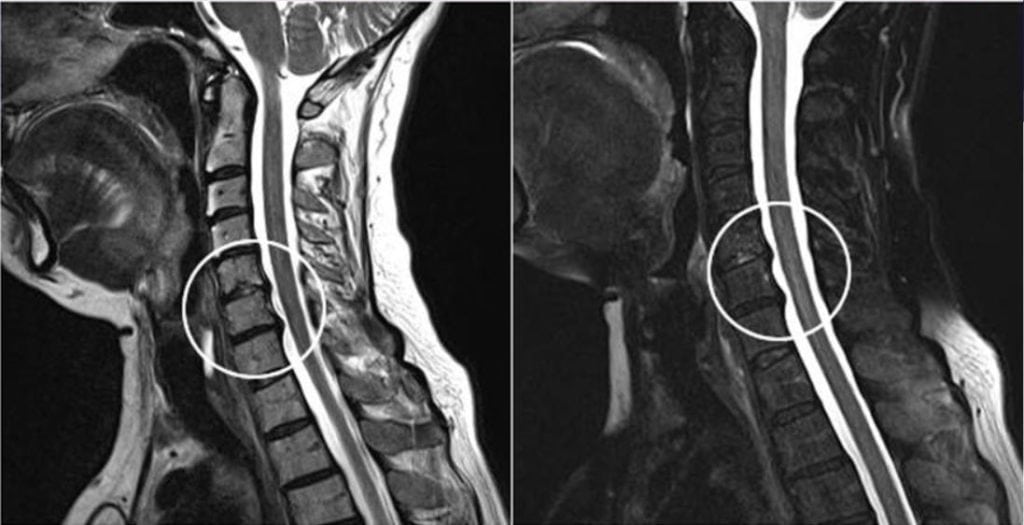

Первичный диагноз выставляется на основании внешнего осмотра пациента, его жалоб, изучения анамнеза. Проводится ряд функциональных тестов для оценки чувствительности и (или) мышечной силы. Обнаружить дорзальную грыжу можно с помощью МРТ. На полученных изображениях видны ее расположение, форма и размеры.